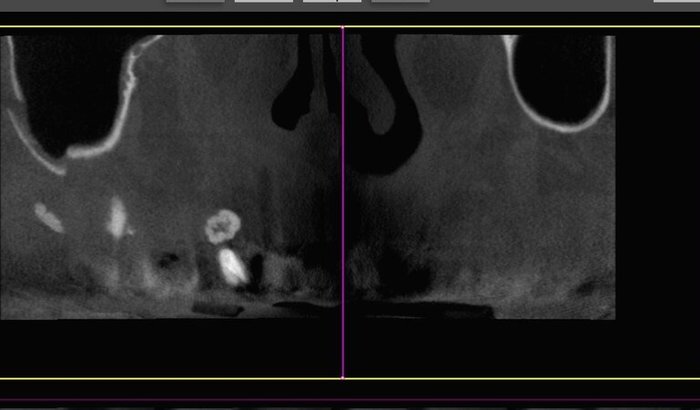

Raiz residual deixada no local da extração. Porisso não cicatrizava.

Fratura óssea no osso do rosto (processo alveolar) com fraguementos ósseos.

Perfuração na parede do seio maxilar

Perfuração da raiz do dente vizinho em furca